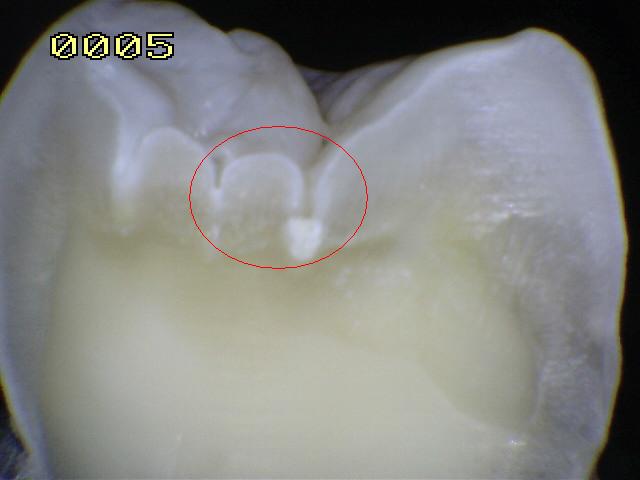

En la imagen izquierda superior

se muestra en color rojo las áreas de estancamiento de la placa

bacteriana en las superficies oclusales, espacios interproximales y los cuellos dentarios. Si la placa

no es

eliminada períodicamente las posibilidad de una lesión cariosa

es alta.

El comienzo de esta lesión es conocida como

"Mancha blanca / marróno Caries Inicial". Si el proceso no se detiene, se

produce una perdida de integridad superficial y/o cavidad en el esmalte.

La fotografía izquierda inferior muestra un premolar que fue extraído por motivos ortodóncicos-periodontales. Antes de la extracción el diente fue

cuidadosamente examinado para ver si estaba cariado.

|

El examen

clínico usando espejo y sonda solo detecto una lesión código 2

en oclusal, y cálculos en el área gingival en las superficies interproximales; no existía

evidencia de deterioro al pasaje del hilo dental entre el

espacio interproximal y el punto de contacto.

Radiografías

de aleta mordible

(bite-wing) fueron tomadas a una exposición normal, y examinadas bajo lente de

aumento; no se encontró ninguna evidencia de caries. El diente fue diagnosticado

con caries en oclusal y fue extraído por motivos

oryodónticos, bajo anestesia local.

No

obstante, examinando el diente extraído después de seco y limpio, puede observarse sin dificultad una pequeña región

blanca sobre la superficie proximal. Esta es la mancha blanca

que representa la más incipiente evidencia macroscópica de

caries; la superficie del esmalte que cubre esta lesión está

intacta y correctamente mineralizada, sin que pueda detectarse

diferencia al tacto con una sonda de exploración.